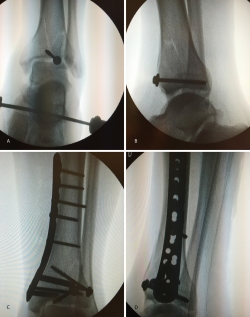

En este caso, es esencial observar las Rx con y sin tracción que nos indican cómo se va a comportar la fractura. Si la fractura es reductible en tracción, es muy probable que podamos realizar una osteosíntesis con restitución completa de la superficie articular. Al realizar la TC, apreciamos la disposición de los fragmentos para marcar una estrategia de reducción bajo control radioscópico y artroscópico, y colocación de los tornillos canulados que fijarán la epífisis distal de la tibia.

Posteriormente, colocaremos la placa en la tibia por vía MIPO realizando una incisión interna, separando la vena safena y deslizando la placa que se fija de manera provisional. Tras comprobar por radioscopia la buena posición del implante, se realiza la fijación definitiva con los tornillos que consideremos adecuados. En el caso de que tengamos que usar un fijador, este sustituye a la placa interna (Figuras 17 a 20).

Figura 17. Caso 3: fractura tipo C. Radiografías sin tracción y con tracción comprobando la reducción.

Figura 19. Colocación del tornillo en el Tillaux con la extremidad en tracción y posteriormente la placa MIPO (minimally invasive plate osteosynthesis).